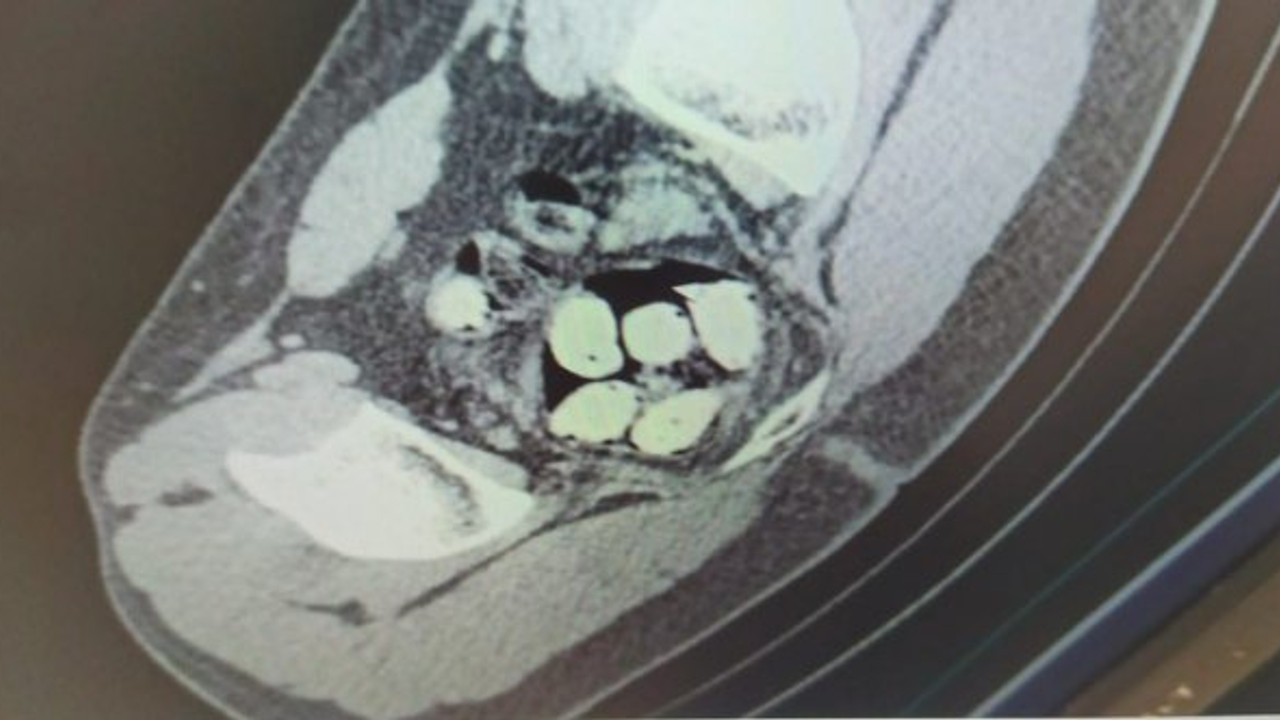

Ardından iç muayenesi yapılan şüphelilerin midesinde uyuşturucu kapsülleri sakladıkları tespit edildi. İran uyruklu 3 şüpheliden S.A.'da 102 kapsül halinde 572 gram metamfetamin, M.S.'de 25 kapsül halinde 270 gram afyon sakızı ve M.H.'da ise 116 kapsül halinde 597 gram metamfetamin, 2 kapsül halinde 20 gram afyon sakızı ve valizinde 230 paket kaçak sigara ile 280 tablet renkli reçeteye tabi sentetik ecza olmak üzere toplam; 218 kapsül halinde 1.169 gram metamfetamin, 27 kapsül halinde 290 gram afyon sakızı, 280 tablet renkli reçeteye tabi sentetik ecza, 230 paket kaçak sigara ele geçirildi.